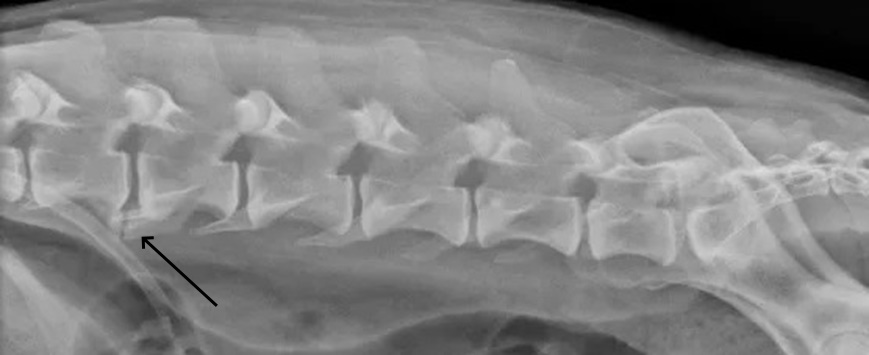

Σπονδύλωση Ο2-Ο3. Πλάγια προβολή οσφυϊκής μοίρας ΣΣ που απεικονίζεται η δημιουργία νέου οστού μεταξύ του σώματος του Ο2 και Ο3.